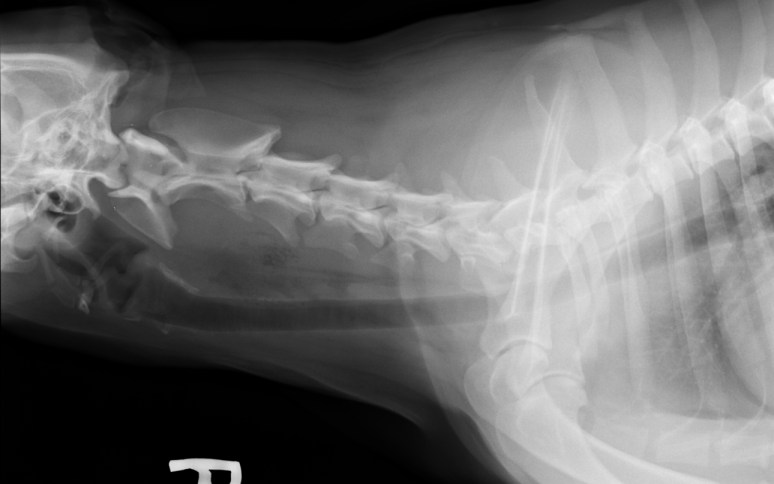

Signalement: Labrador de 2 ans, femelle stérilisée.

Histoire clinique: Dysphagie, douleur au cou, boiterie de non appui MTG, parésie MPs pire a gauche. Lésion suspectée au niveau cervical caudal latéralisée à gauche.

La lésion semble localisée au niveau de l’atlas. Serait-ce une fracture de cette vertèbre cervicale qui entraîne une dysphasie par compression de l’oesophage et douleur au courant? Si fracture il y a, quelle en serait la cause ? Est-ce que la compression de la moelle épinière à ce niveau pourrait être responsable de la paresie des MPs et de la boiterie de non appui au MTG?

Salut Robert ! La forme de l’atlas est due à sa rotation axiale, entraînant les ailes dorsalement et ventralement. C’est pour ça aussi que le processus odontoïde est si évident. On peut donc dire que ce processus est intact. Continue ton exploration des images… 😉